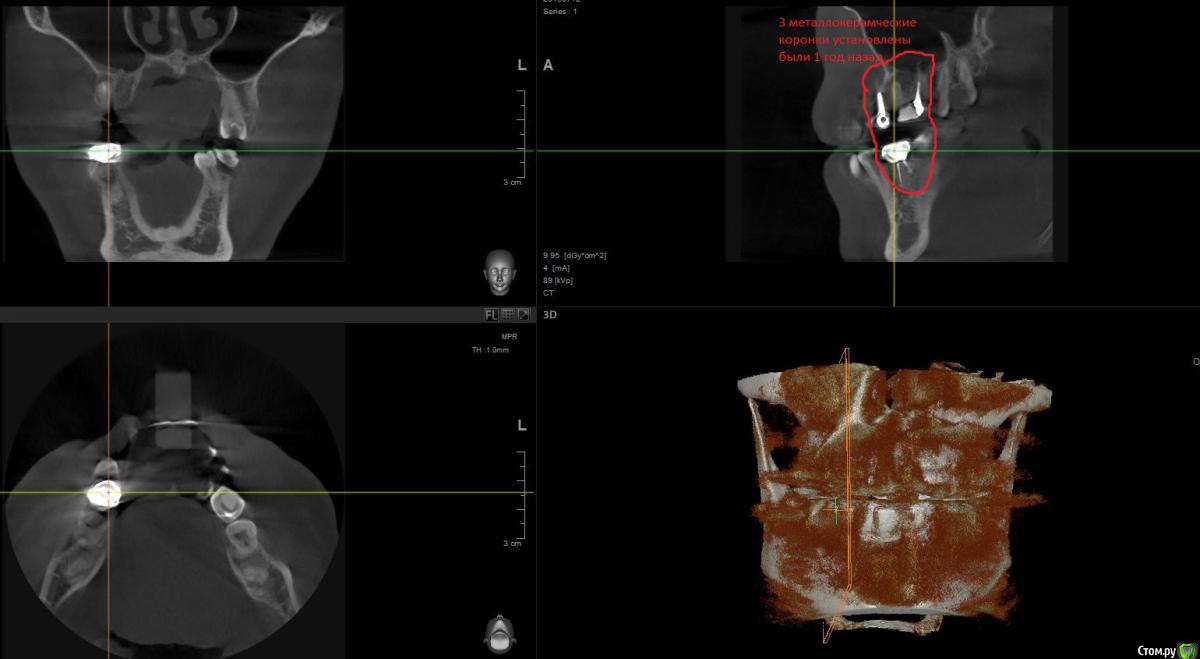

1 год назад были установлены 3 коронки. см Фото. После появления свища над верхней коронкой обратился к стоматологам.На фото 2 верхние коронки уже спилены и начато повторно лечение одного зуба,за мой счет конечно.

По результатам снимков след.вывод. Две верхние коронки снимать и лечить каналы , так там воспаление. Под нижней коронкой небольшое воспаление,но сказали пока его не трогать ,но взять под наблюдение.

post-48565-0-48636800-1469537769_thumb.jpg